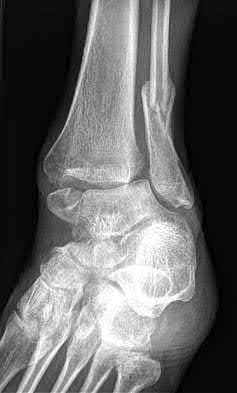

A 25-year-old female is involved in a motor vehicle collision. She presents with the isolated injury seen in Figures A through D. Her leg is swollen but her skin is intact. She has no clinical signs of compartment syndrome. Which of the following treatment options will allow for maintenance of fracture alignment and minimize the risk of soft tissue complications?

The patient presents with a closed distal third metaphyseal-diaphyseal distal tibia fracture with simple intra-articular extension. Immediate intramedullary nailing along with percutaneous fixation of the articular component provides appropriate restoration of length, rotation and alignment and minimizes the risk of wound complication.

Displaced distal third tibia fractures may be associated with simple intraarticular extension. Operative treatment of intra-articular distal tibia fractures has historically been performed with open reduction and internal fixation. Early open reduction and plate fixation of pilon fractures has been associated with high rates of infection and wound complication. In select patterns with simple articular extension, percutaneous screw fixation and medullary nailing may provide appropriate reduction with minimal soft-tissue risk.

Figures A and B demonstrate a distal third tibial shaft fracture with simple intra-articular extension. The axial and coronal CT cuts in Figures C and D further clarify the articular injury. Illustrations A and B demonstrate a comminuted distal third tibial fracture with simple intra-articular extension. Illustrations C and D are fluoroscopic images of the same injury after intramedullary nailing and percutaneous fixation of the articular component.